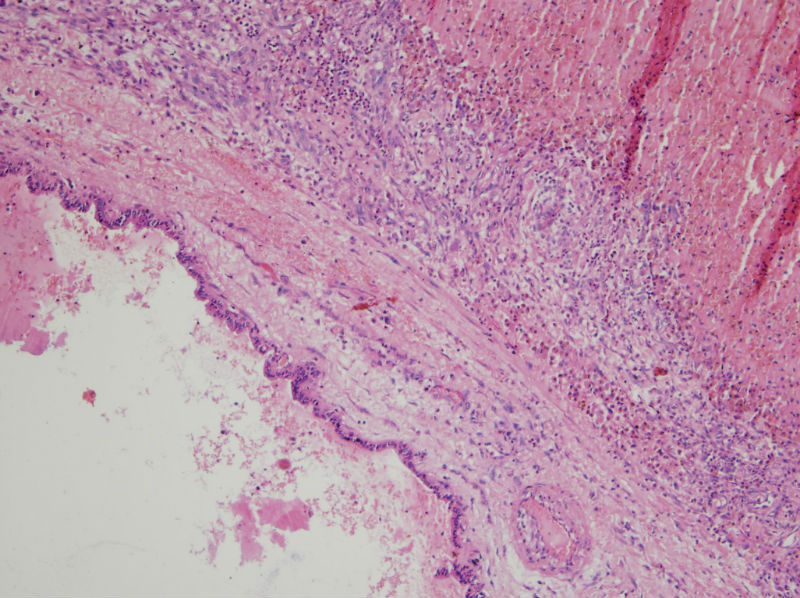

甲状腺囊肿,请老师们指教

男,44,甲状腺囊肿.直径1.5公分,内流清亮液

补充,,包膜不完整..囊内壁就是图2,图3..

结节性甲状腺肿伴囊性变。图2右上角的滤泡上皮似乎有些嗜酸性变。总之:良性病变。图13伴有出血。

结节性甲状腺肿伴囊性变     还可见囊壁周围伴有感染吧。

该囊肿不与舌骨相连,不是甲状舌骨囊肿。上皮下淋巴细胞不丰富,不是腮裂囊肿。

结节性甲状腺肿伴出血、囊性变。囊肿边上的滤泡大小不一,纤维组织增生,还可见炎细胞浸润。

结节性甲状腺肿囊性变伴周围慢性炎细胞感染。

结节性甲状腺肿伴出血、囊性变。